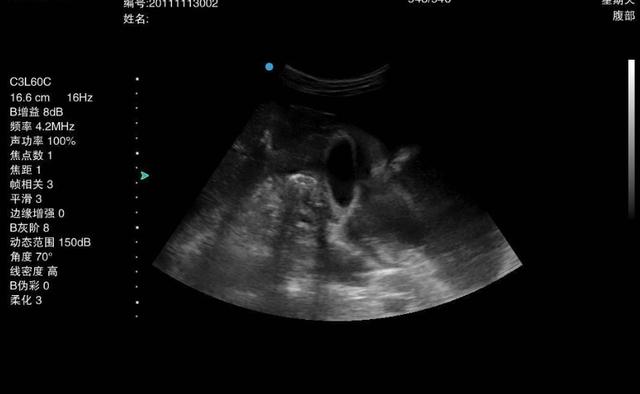

到医院后,医生建议他做一个胃镜检查,这一检查才知道,小金得了胃癌,小金很疑惑:近年来饮食上都很清淡,没有乱吃什么,就是有一个单纯的胃炎病,怎么还变成胃癌了呢?